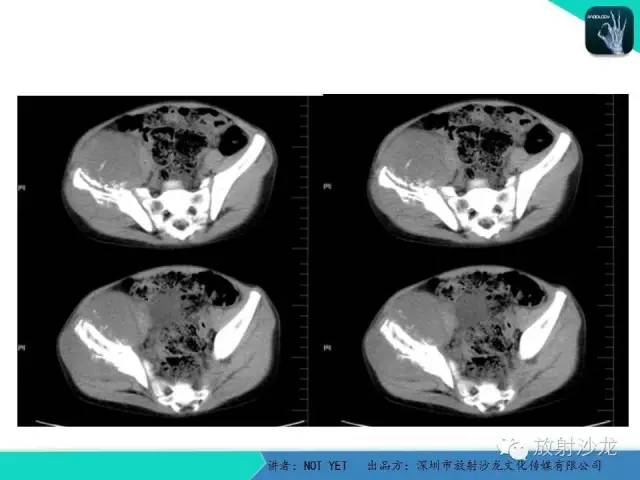

【病例】右侧髂骨Ewing肉瘤1例CT影像表现